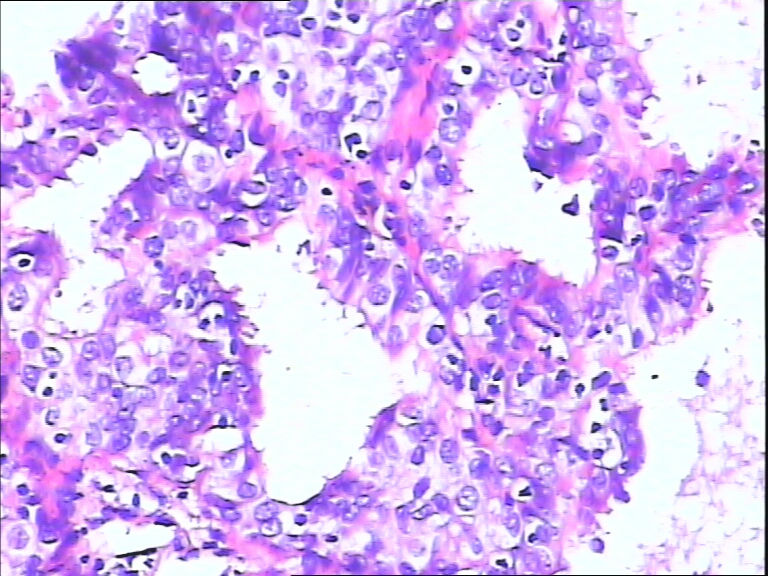

女,43y

左输卵管积液

输卵管长4.5cm;直径:0.8cm

• 请教:输卵管!图4

图4

输卵管增生性上皮病变。

慢性炎伴上皮增生

良性,炎症改变

考虑炎症